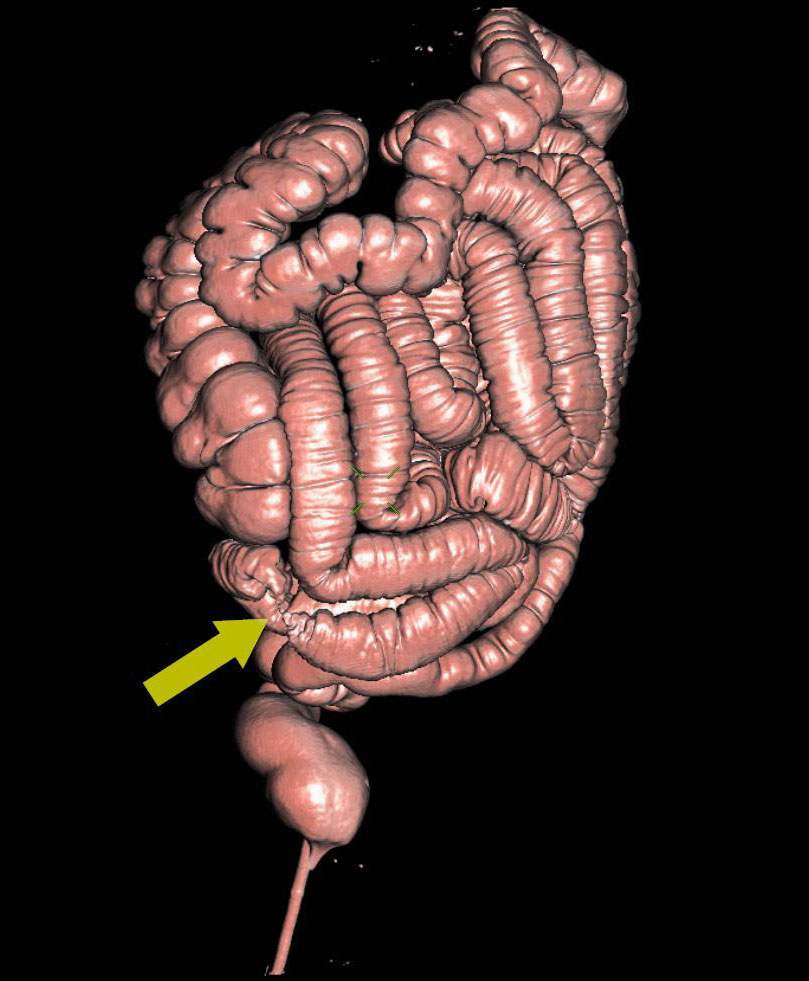

3D- реконструкция при исследовании пищеварительной системы: (Виртуальная гастро; колоноскопия)

Виртуальная колоноскопия — это метод лучевой диагностики, позволяющий визуализировать отделы толстой кишки. Виртуальная гастроскопия, аналогичный метод позволяе…